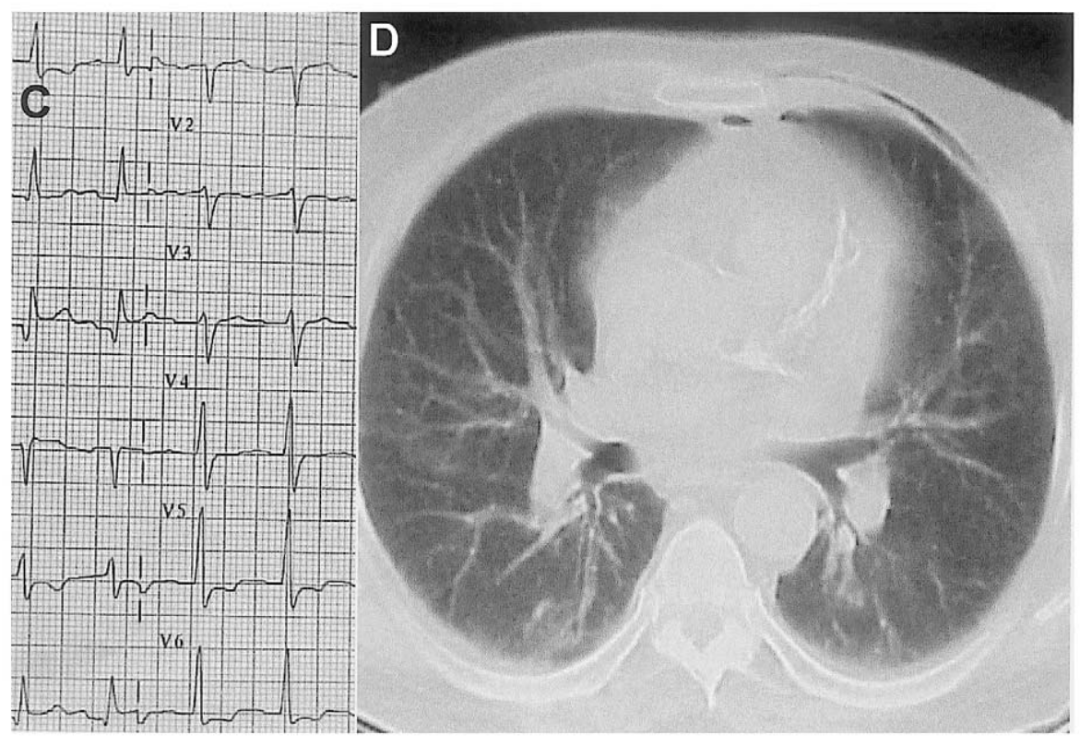

别慌,心电图带你抽丝剥茧找真凶|心电图_新浪财经_新浪网